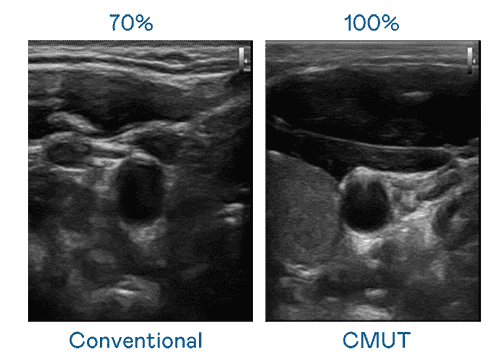

CMUT 技术是一种用电容式微机电元件来产生超音波讯号的技术。。。与传统 PZT 压电式技术相比,,CMUT 频宽增加 30%,,,,更宽频的超音波讯号让影像解析度大幅提升,,,是实现高影像品质医疗超音波扫描、、、、促进精准医疗发展的关键技术。。。。

大频宽带来超清晰影像

超音波影像的解析度高低,,,,首先取决于探头能发出的讯号频宽。。918.COM CMUT 可提供高清晰的超音波讯号,,,提供高频宽、、高灵敏度、、、影像纹理细节更高的超音波影像,,,,协助医护人员缩短影像判读时间及利用精准的医疗影像进行诊断。。